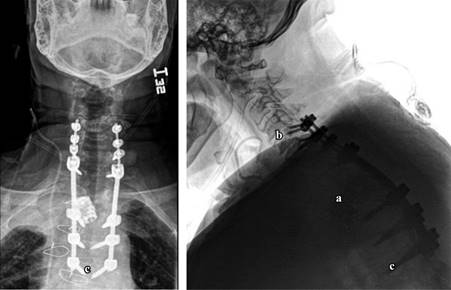

Once confirmed the integrity of the anterior dura, a two-level expandable cylinder is placed restoring stability, as well as placement of broad-spectrum antibiotic granules (Figure 4). Stability of the osteosynthesis system besides the integrity of the cardiopulmonary elements are corroborated (Figure 5), a deep thoracic drainage tube is placed and the incision was closed in layers as usual (Figure 6).